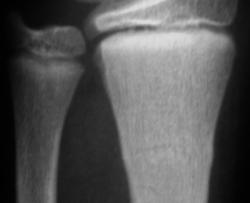

Травма. Пациент направлен хирургом в рентгеновский кабинет для рентгенологического исследования лучезапястного сустава.

Кроме основного – "зеленая ветка" – другой недостоверен: может быть артефактом. На боковой рентгенограмме полоса слишком чёткая для нерезкого в целом снимка, похожа на полосы в области запястных костей. Там нет переломов? Подмигивает В прямой проекции обе линии принадлежат поднадкостничному перелому.